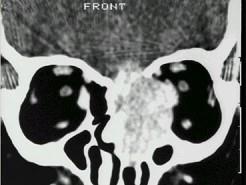

问题 男性50岁,涕中带血半年,体检发现右侧颈部多个硬结,CT扫描如图所示,请选择正确的描述和结论 ( )

选项 A、考虑为右侧筛窦黏液性囊肿 B、考虑为右侧筛窦癌 C、软组织影累及对侧筛窦、右侧上颌窦 D、右侧眶内壁、上颌窦壁及颅底骨质破坏 E、右侧筛窦内见软组织块影,边缘不规则

答案 BCDE